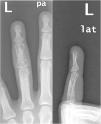

Varón de 42 años, natural de Marruecos, sin antecedentes de interés. Acudió a consultas de Atención Primaria por un cuadro de un año de duración de tumefacción en la falange media del cuarto dedo de la mano izquierda, no dolorosa en reposo pero sí a la presión. No refería antecedentes traumáticos ni ninguna otra sintomatología. Externamente, la piel y el aspecto de la región referida eran rigurosamente normales. Se decidió realizar una radiografía del dedo afecto, en la que se observaron múltiples lesiones óseas líticas con morfología en «panal» en la falange media (fig. 1). Ante estos hallazgos, el servicio de Radiodiagnóstico recomendó completar el estudio con una RM de mano, que confirmó estos hallazgos y valoró mejor la extensión de los mismos, así como el respeto de los espacios articulares (fig. 2A). Ambas pruebas, tanto la radiografía como la RM, plantearon el diagnóstico de sarcoidosis ósea. Se completó el estudio con una radiografía simple (fig. 2B) y una TC torácica, que demostraron adenopatías hiliares bilaterales y un área en vidrio deslustrado en el lóbulo medio. Se remitió al paciente al servicio de Neumología para la toma de biopsia. Tras la biopsia transbronquial de una de las adenopatías, el resultado anatomopatológico fue compatible con sarcoidosis. El diagnóstico final fue de sarcoidosis estadio ii con afectación ósea.

Imagen de resonancia magnética potenciada en T2 con supresión grasa centrada en el cuarto dedo de la mano izquierda (A): se aprecia una alteración de la señal que afecta de forma difusa a la falange media del cuarto dedo con áreas pseudonodulares marcadamente hiperintensas en secuencias T2 con áreas de esclerosis interpuestas (aspecto en «panal/encaje»). Radiografía simple de tórax posteroanterior (B) que pone de manifiesto un engrosamiento hiliar bilateral que evidencia la presencia de adenopatías (confirmadas posteriormente con TC).